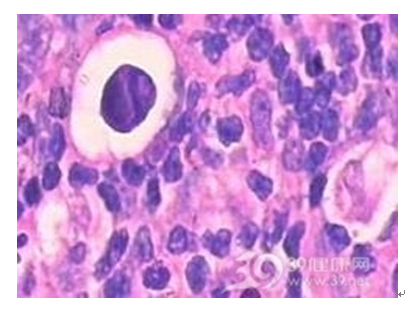

慢性淋巴结炎

慢性淋巴结炎多继发于头、面、颈部的炎症病灶。淋巴结不同程度的肿大,散见于颈侧区或颌下、颏下区。可略硬但表面光滑,能活动,可有轻度压痛或不适。慢性淋巴结炎本人不需要治疗,检查时应注意寻找原发炎症灶。除颈部各区外还应仔细检查头皮、外耳及口腔、扁桃体、牙龈等隐藏部位。还可按肿大淋巴结的淋巴接纳区找寻原发病灶。